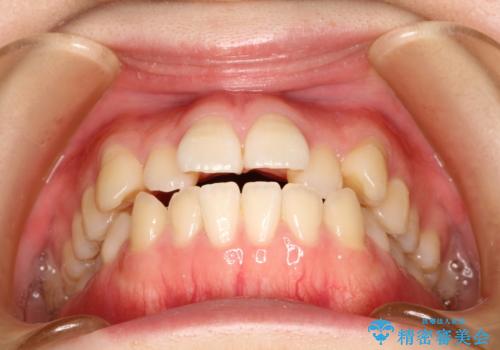

- 前歯をきれいにしたいとのことで来院されました。

前歯にがたつきがあり、上下の歯が咬み合っていない状態でした。

患者様が歯を抜きたくないとのご希望があったので、インビザラインで非抜歯矯正をすることとなりました。